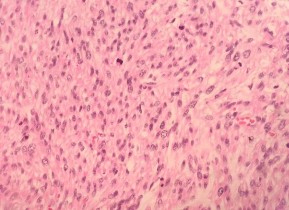

(Bệnh nhân: Triệu Tài V.)

HE x 100: Các tế bào u hình thoi, nhân bàu, bào tương hồng, sắp xếp thành bó | HE x 400: Không rõ màng nhân, giàu nhân chia. |

SMA: Dương tính mạnh bào tương | DESMIN: Dương tính bào tương |

CALDESMON: Dương tính với bào tương | DOG 1: Âm tính với tế bào u |